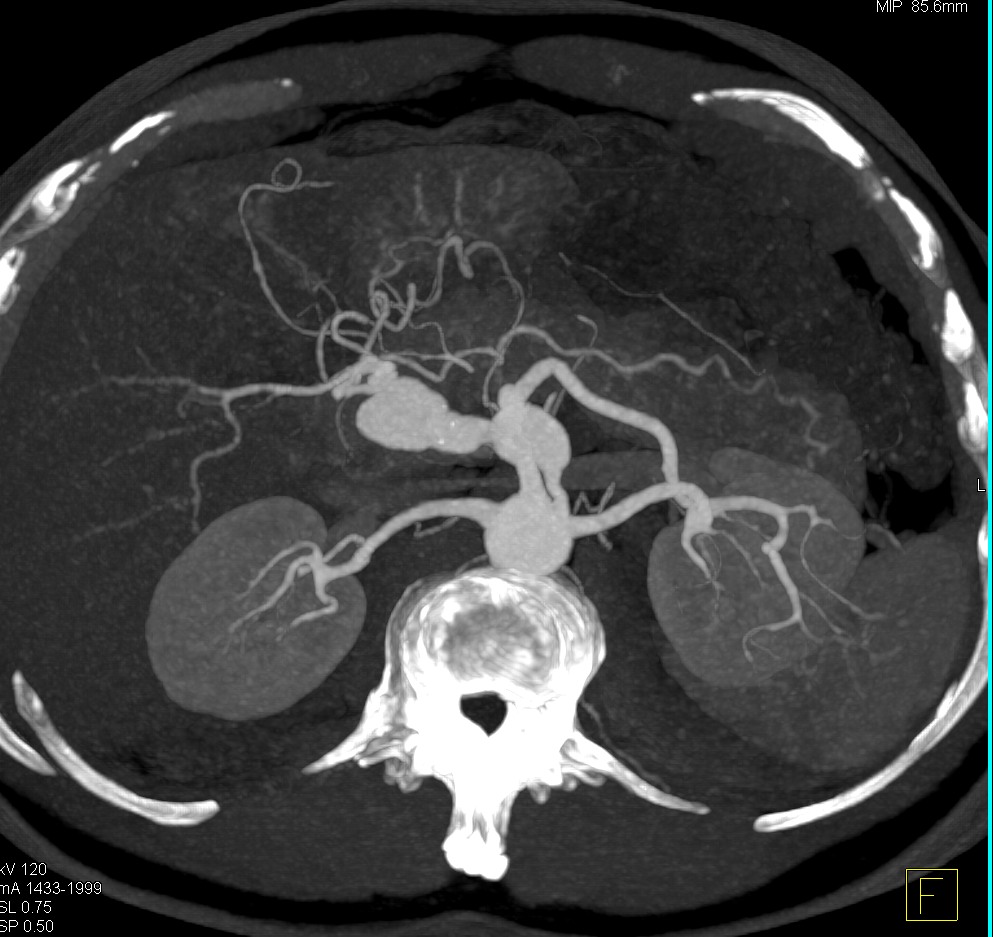

@ctisus

Elliot K Fishman / CTisus.com

12 hours

Hepatic Artery Aneurysm